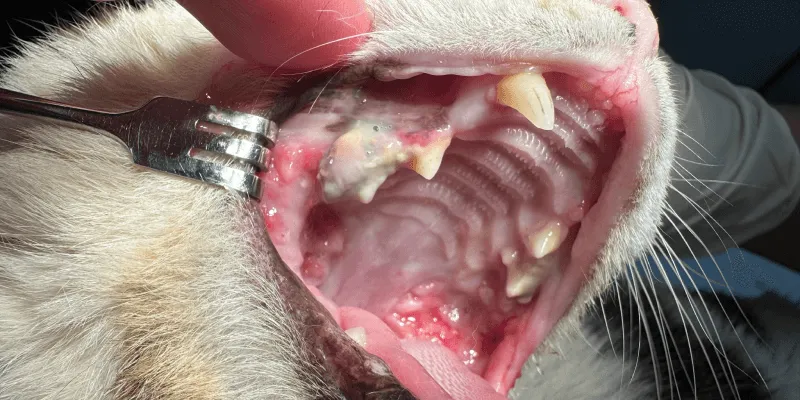

猫の慢性歯肉口内炎(FCGS)

歯肉だけでなく、頬の内側や舌など、口の中の非常に広い範囲で炎症を起こします。とても痛みが強いため、よだれが増え、食事もとれなくなってしまいます。

免疫の関与した複雑な病態が疑わており、症状をコントロールするためにステロイド剤などによる内科治療が行われます。

一方、この病気は抜歯による治療もすすめられます。抜歯により完治、または薬の量を減らし、生活の質を大幅に改善できる可能性があります。ただ、抜歯をしても再発したり、あまり効果が得られない場合もあるため、ご家族の御意向もお伺いしながら、治療プランをご提案します。